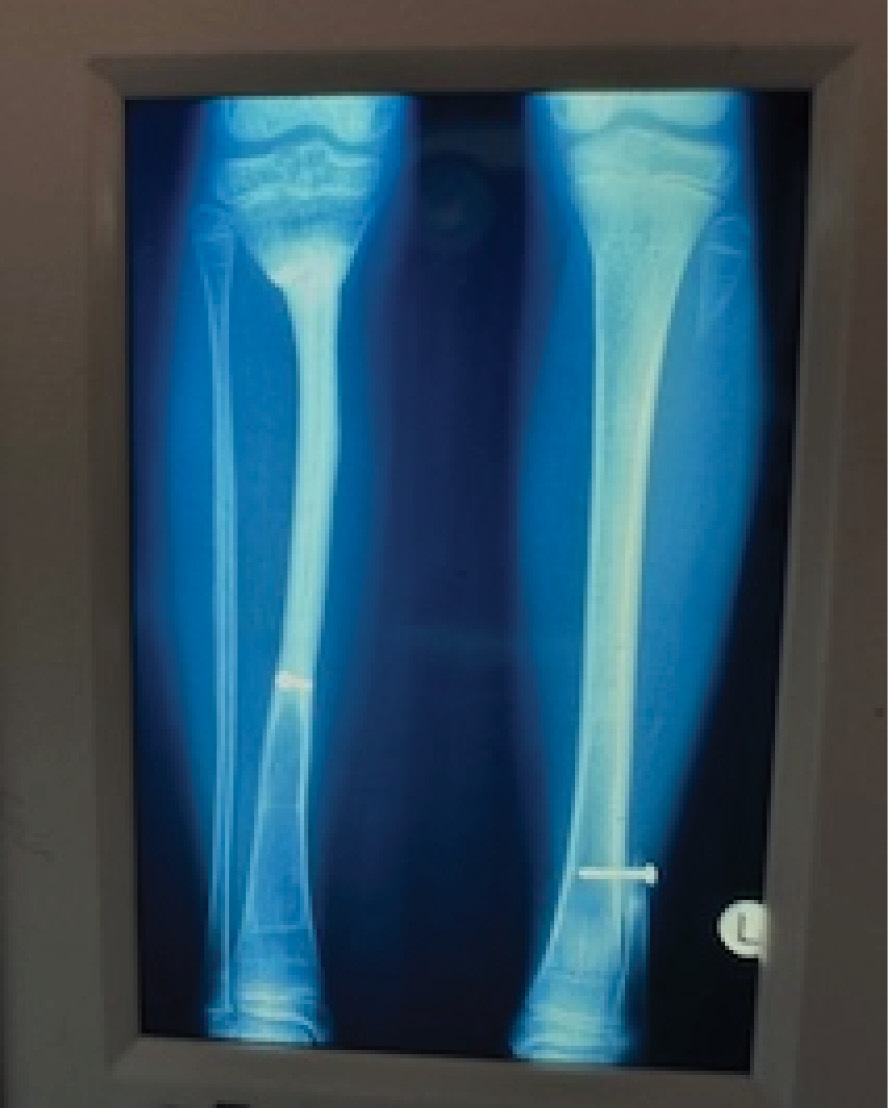

A two-stage transfer of the ipsilateral fibula was then attempted by our orthopaedic team, based on a muscle pedicle and fixed to the tibia with screws. Unfortunately, the bone failed to knit at the upper end. It developed a pseudarthrosis and the patient was left with a flail leg (Figure 2). Amputation was recommended but ‘if a skin flap can be transferred successfully with microsurgery why not bone, and which one?’

On 20 January 1973 the free groin flap was transferred successfully at PANCH for the first time.2,3 One week later, a 19-year-old young man was admitted to the same hospital with a shotgun injury to his left leg (Figure 1A). The wound included skin, most of the anterior muscle compartment and a 12.5 cm defect of the tibia (Figure 1C).

The foot was sensate and the fibula was intact. So we set about reconstruction. The defect was debrided, healed initially with a split skin graft and then a free groin flap was attempted but abandoned because the groin vessels were very small and the recipient anterior tibial vessels badly damaged. However, because we had performed a lateral to medial dissection of what was now an expanded iliofemoral flap,2 that included the superficial inferior epigastric as well as the superficial circumflex iliac vessels, we were able to tube the flap and transfer it in stages to the leg (Figure 1B).